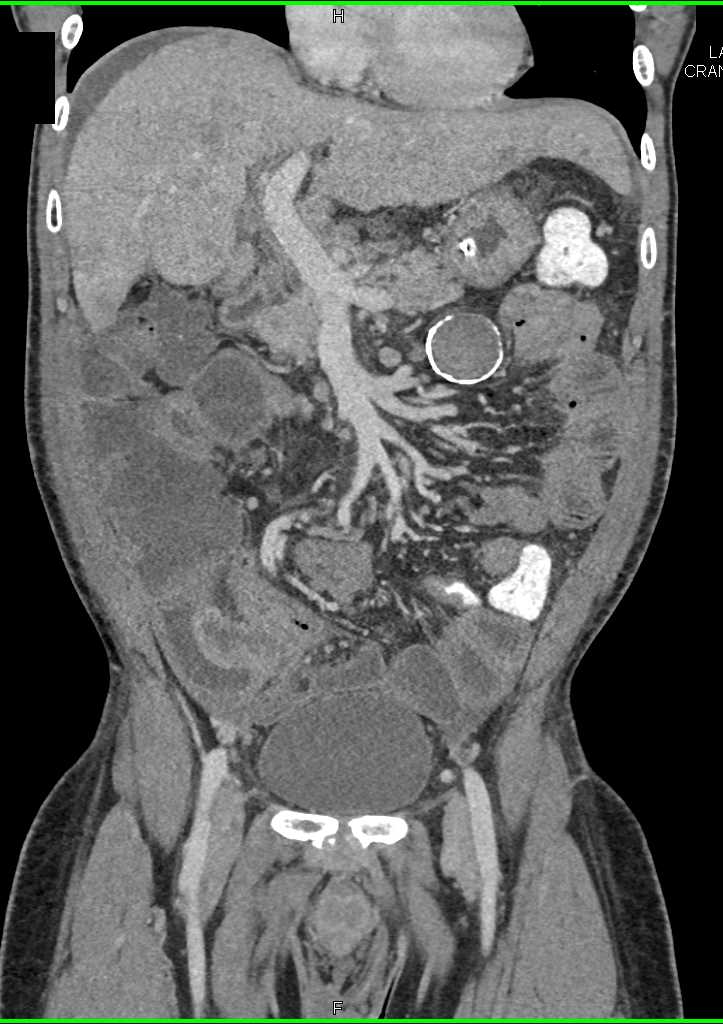

Small Bowel Carcinoma with Carcinomatosis